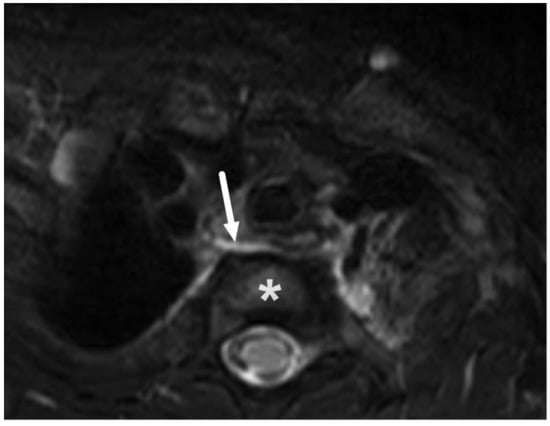

4.2. Retropharyngeal Abscesses and Suppurative Lymphadenitis

| Abscess | T1 SE T2 Dixon (water) DWI post-contrast T1 Dixon (water) | Non-enhancing collection with low ADC values enclosed in abnormally enhancing soft tissue edema. | Detection of an abscess usually requires operative consideration and exact abscess location, and extensions are useful in operative planning. | Abscesses may have an intermediate T2 signal content; blood products and/or postoperative status may complicate abscess assessment; necrotic lymph nodes may be misinterpreted as suppurative lymphadenitis. |

| Complications | Whole protocol | Abscess extending to multiple deep neck spaces, mediastinis, venous thrombosis, and airway compromise. | Detection of potentially life-threatening conditions. | Magnetic resonance angiography (MRA) or CECT may be needed to diagnose venous thrombosis; defining airway compromise is difficult. |